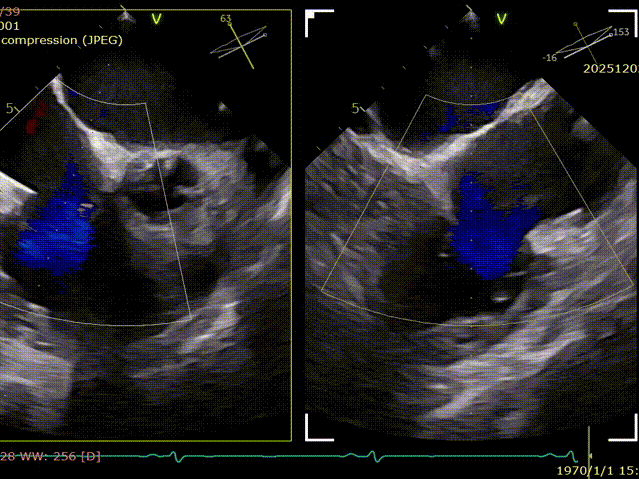

During the procedure, close collaboration was maintained with Dr. Yang Yan (anesthesiologist, Department of Anesthesiology) and Dr. Niu Ming (echocardiography specialist, team of Director Zhai Hong, Department of Cardiac Ultrasound). Guided by transesophageal echocardiography and assisted by DSA imaging, the tricuspid annular structure and regurgitation jet direction were precisely assessed. Ultimately, two 12T K-Clip® devices were successfully implanted. Immediate postoperative echocardiographic evaluation showed a significant reduction in tricuspid regurgitation from 4+ preoperatively to 1+, with a marked decrease in annular area. The surgical outcome was satisfactory.

Evaluating the effect.

Coronary angiography after the deployment of the second clip.